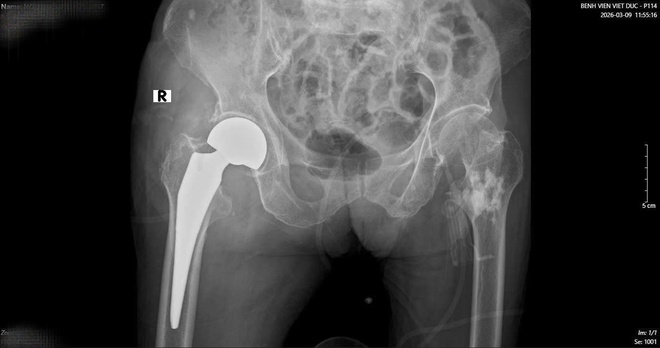

Hình ảnh phim X-quang cụ bà 89 tuổi nhập viện gãy cổ xương đùi phải và hình ảnh chụp CT ổ bụng và phát hiện khối u ruột non gây lồng ruột.

Sau một tuần, khi các chỉ số sức khỏe ổn định, cụ bà tiếp tục bước vào cuộc đại phẫu thứ hai. TS.BS Hoàng Ngọc Sơn đã trực tiếp phẫu thuật thay khớp háng cho cụ. Nhờ sự chuẩn bị kỹ lưỡng của đội ngũ y bác sĩ, ca mổ đã thành công tốt đẹp.